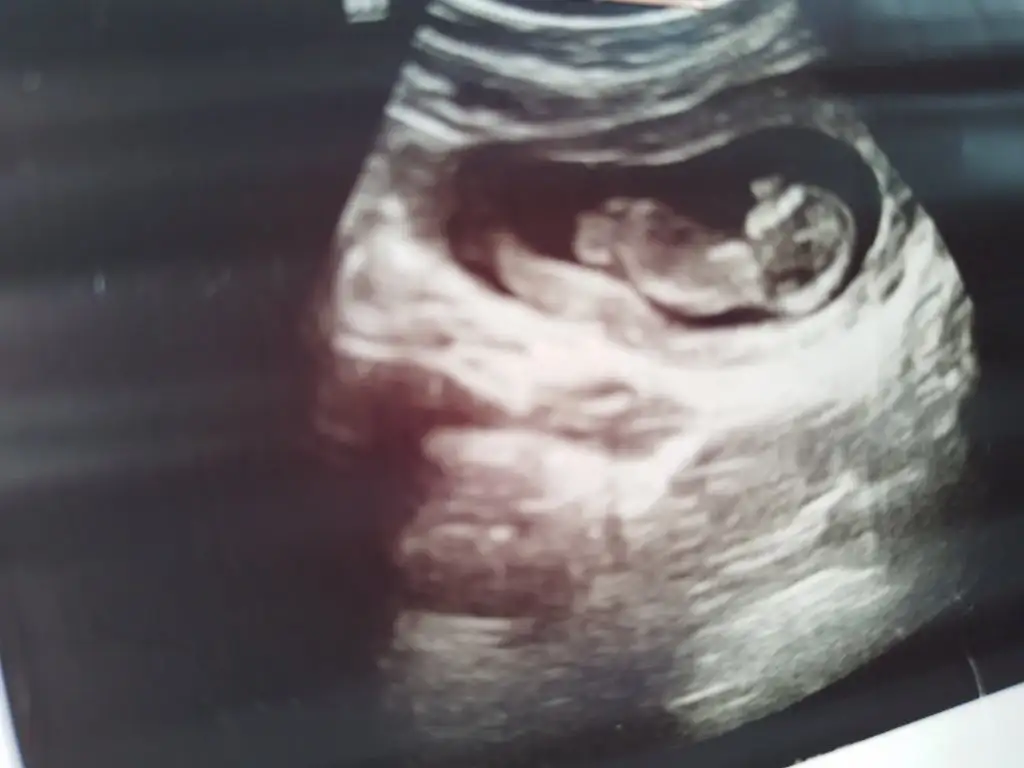

Arkadaşlar merhaba daha önce burada ultrason fotoğrafına bakıp cinsiyet tahmin edenleri görmüştüm benim içinde bi heyecan olur:) var mıdır tahmininiz normalde 12+4 üm ama ultrasonda 13 haftalık görünüyor